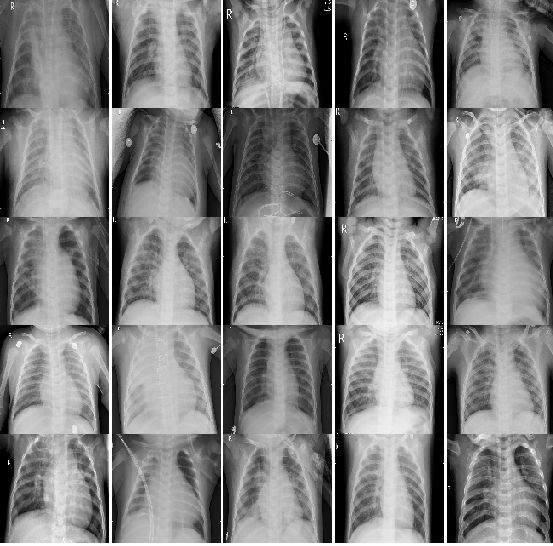

2.2.2 有肺炎的20个病例的CT图片:

multipleImages = glob('chest_xray/train/PNEUMONIA/**')

i_ = 0

plt.rcParams['figure.figsize'] = (10.0, 10.0)

plt.subplots_adjust(wspace=0, hspace=0)

for l in multipleImages[:25]:

im = cv2.imread(l)

im = cv2.resize(im, (128, 128))

plt.subplot(5, 5, i_+1) #.set_title(l)

plt.imshow(cv2.cvtColor(im, cv2.COLOR_BGR2RGB)); plt.axis('off')

i_ += 1